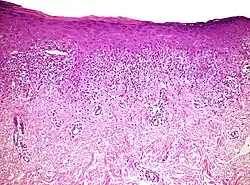

| Lichen planus | Irregular epidermal hyperplasia with a jagged “sawtooth” appearance, compact hyperkeratosis or orthokeratosis, foci of wedge-shaped hypergranulosis, basilar vacuolar degeneration, slight spongiosis in the spinous layer, and squamatization. The dermal papillae between the elongated rete ridges are frequently dome shaped. Necrotic keratinocytes can be observed in the basal layer of the epidermis and at the dermal-epidermal junction. Eosinophilic remnants of anucleate apoptotic basal cells may also be found in the dermis and are referred to as “colloid or civatte bodies”. Whickham striae are usually seen in the areas of hypergranulosis. Vacuolar degeneration at the basal layer may be noted leading to focal subepidermal clefts (Max Joseph spaces). Squamatization occurs as a result of maturation and flattening of cells in the basal layer. It happens in areas of marked hypergranulosis with prominence of the sawtooth pattern of rete ridges. Wedge-shaped hypergranulosis can occur in the eccrine ducts (acrosyringia) or hair follicles (acrotrichia). In the hypertrophic subtype, the associated hyperkeratosis, parakeratosis, hypergranulosis, papillomatosis, acanthosis, and hyperplasia markedly increased with thicker collagen bundles forming in the dermis. Moreover, the rete ridges are more elongated and rounded as opposed to the typical sawtooth pattern. In atrophic LP, loss of the rete ridges and dermal fibrosis is prominent. In vesiculobullous LP, the disease progression is quicker. Hence, some of the distinctive features such as hyperkeratosis, hypergranulosis, or dense lymphocytic dermal-epidermal infiltrate may not be present. LP lesion may resolve with residual hyperpigmentation caused by a persistent increase in the number of melanophages in the papillary dermis.[9] | ![]() |